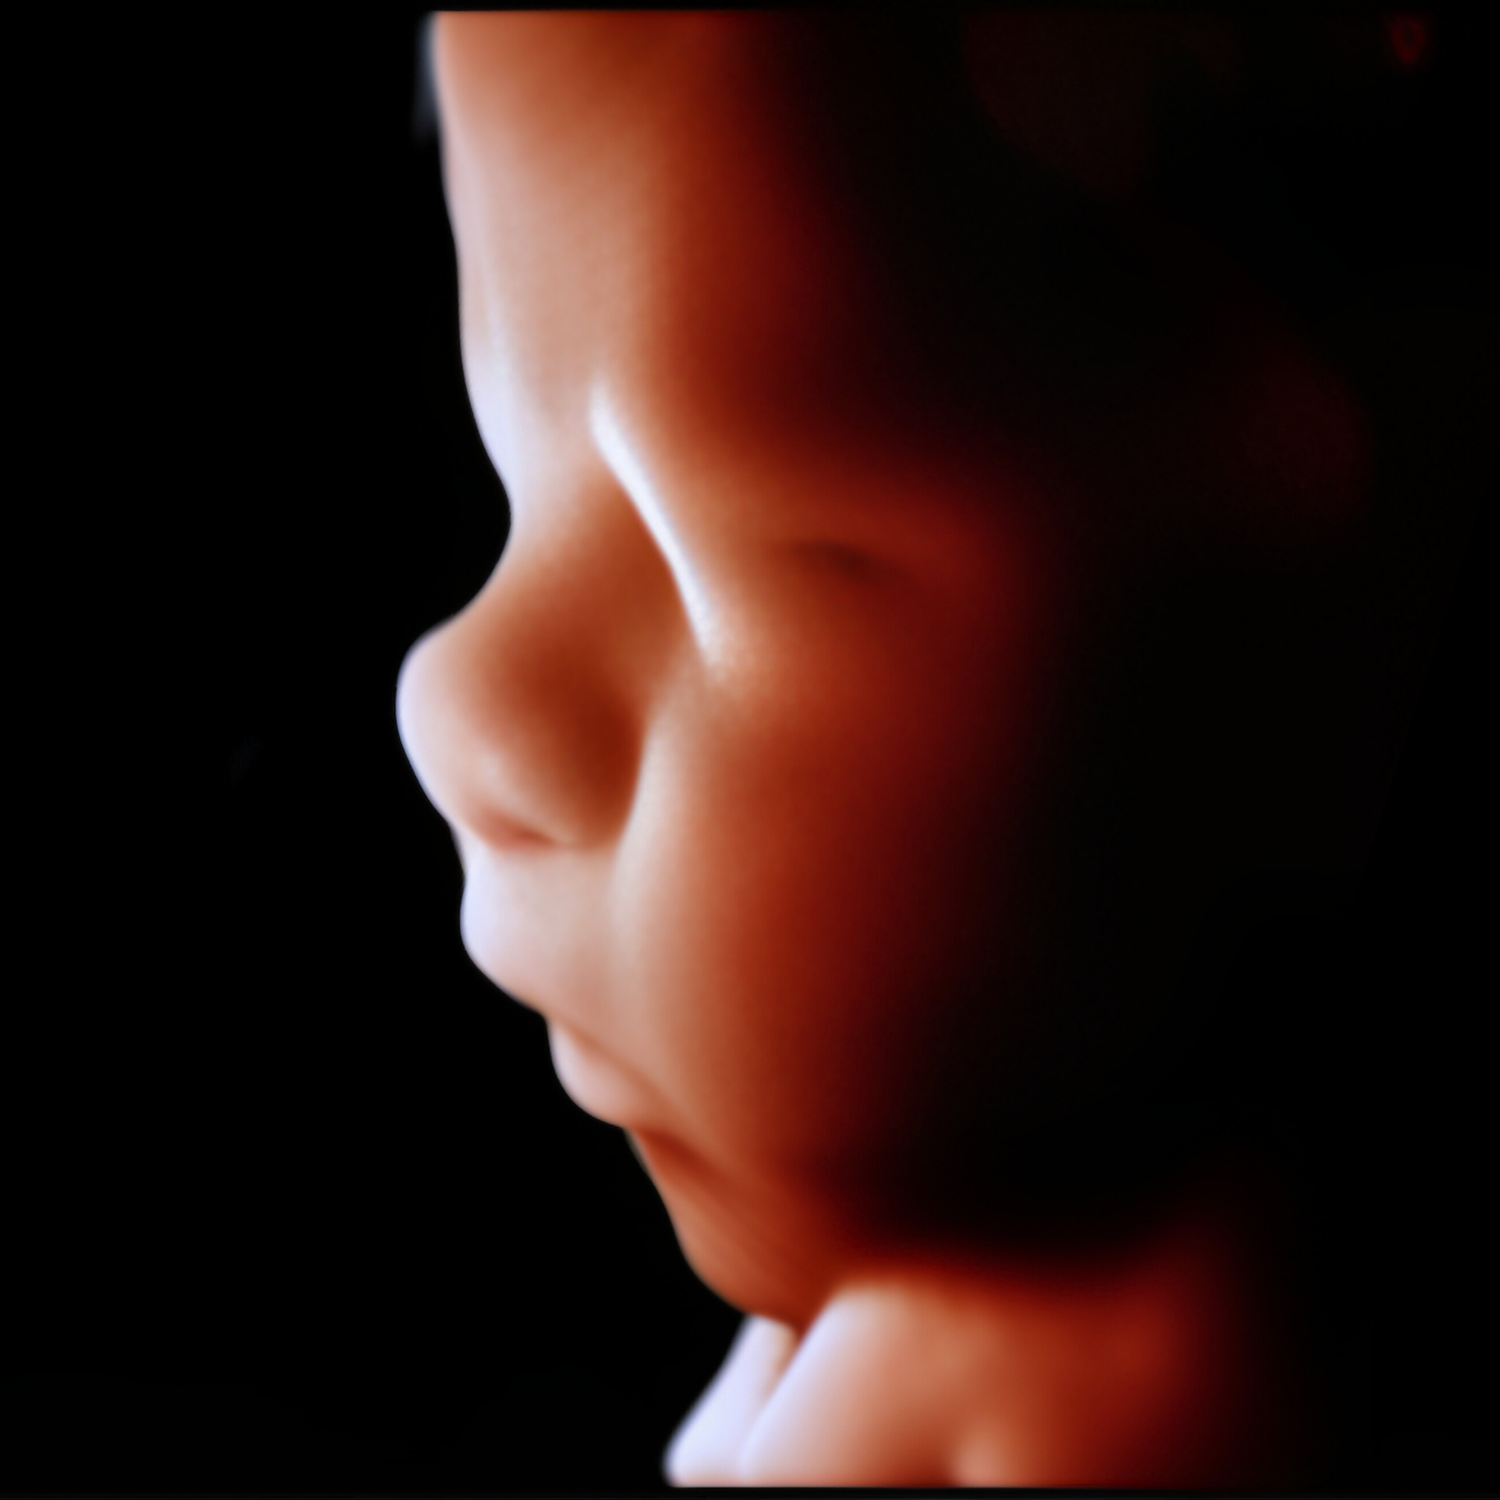

Morfológica 2D

Realizarlo ideal entre las 20 a 24 semanas.

Una de las ecografías más importantes del embarazo. Este es el momento para descartar anomalías fetales de órganos, sistemas y evaluar la circulación placentaria.